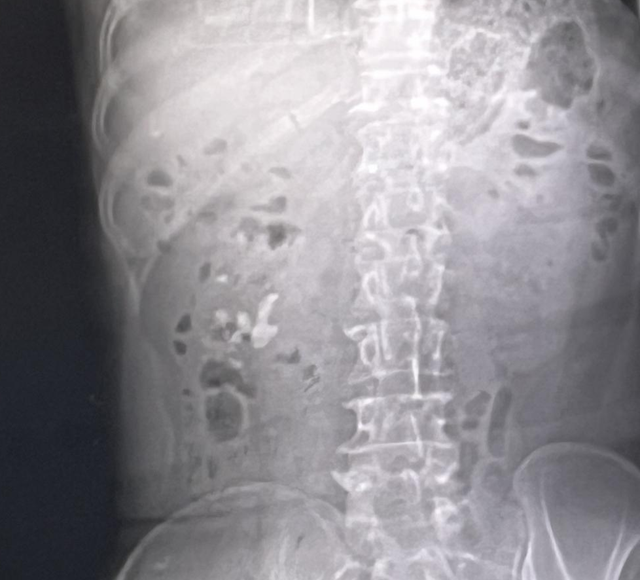

驻马店市中心医院近期收治一名因长期饮水不足、饮食失衡导致肾结石的12岁患者,刷新了公众对结石疾病低龄化趋势的认知。该院妇女儿童医院成人、小儿泌尿外科主任徐海亮指出,肾结石的形成与日常饮食习惯密切相关,平时要注意饮水量控制、膳食结构调整、矿物质摄入,建立"吃出来的健康防线"。

徐海亮说,肾结石的形成与多种因素有关,包括尿液中矿物质的浓度过高、尿液酸碱度失衡等。当尿液中的某些成分,如钙、草酸、尿酸等浓度过高时,它们可能会结晶并聚集成团,最终形成结石。肾结石的症状多种多样,可能包括腰痛、血尿、尿频、尿急、尿痛等。若结石较大或卡在尿路中,还可能引发肾积水、肾功能受损等严重后果。所以预防肾结石需要对日常饮食和生活方式进行干预。

徐海亮提醒:“得了肾结石之后,一定要注意改变平常的饮食习惯和饮水习惯,注意增多和减少这四个字,首先要增多平常的饮水量,直至使尿液颜色变清亮,这是初步评判多饮水的一个标准。同时要减少含钙食物的摄入和高草酸食物的摄入,减少动物内脏、啤酒等高嘌呤食物摄入,平常要注意低盐饮食,减少高热量饮料摄入。如果结石直径小于六毫米,可以通过运动、跑跳、喝水,配合药物治疗,促进结石的自然排出。如果结石直径大于六毫米,建议体外碎石或者进行手术治疗。”